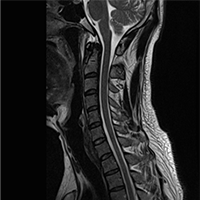

• Normal Cervical

MRI

• Cervical Disc

Herniation at C5/C6